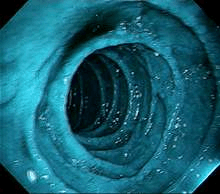

mBLU uses multi-LEDs of wavelength between 400-700nm & 450nm for enhanced mucosal and submucosal tissue visualisation. The brighter and clearer images provided by the mBLU technology enable Image-Enhanced-Endoscopy (IEE) and help detect and characterize lesions/polyps better, thus improving the chances of detecting early-stage cancer and providing high-quality lifecare.

mBLU1 enhances mucosal tissue structure visualisation, improving diagnostic yield and lesion characterization. Its spectral imaging helps detect early-stage esophageal cancer, Barrett’s dysplasia, and minimal esophagitis.

mBLU2 leverages Blue Light technology to enhance submucosal vascular microarchitecture visibility, improving early cancer detection. mBLU 2 is optimised to offer a close-up or detailed view to penetrate the superficial epithelium and differentiate adenoma from invasive cancer.

Unlike conventional xenon-based white light, our White Light Endoscopy (WLE) technology equips endoscopes with small LED lamps fixed at the end of the endoscope tip. LED-powered White Light Endoscopy (WLE) enhances vascular microstructures by illuminating selectively in the 400–700 nm spectrum. This technology delivers higher-intensity white illumination, sharper contrast, clearer imaging, and improved diagnostic accuracy.